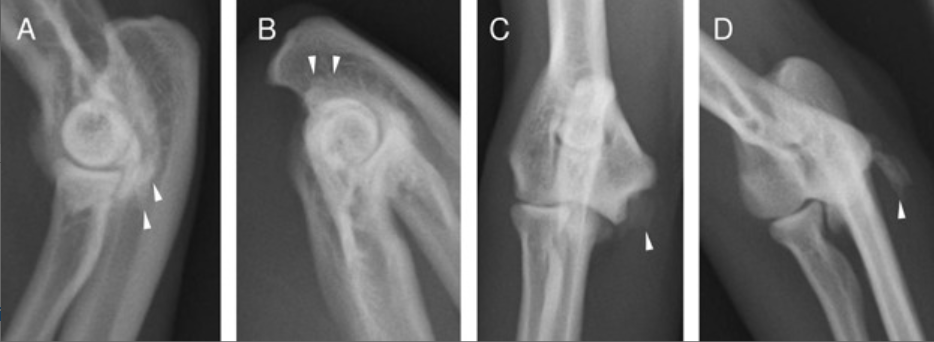

Radiographs of the right elbow of cat 14. (A) An irregular and rounded edge of the medial epicondyle (white arrow heads) in extended mediolateral projection. (B) Flexed mediolateral projection. (C) Compact, irregular new bone formation (white arrow heads) on the medial epicondyle appears close to the humeral condyle in the straight craniocaudal projection. (D) Oblique, supinated projection.

Imaging: Common findings included new bone formation, bony spicules, and intra-articular free joint bodies (53%). Early stages of MHE without mineralization were better detected with CT than radiographs.